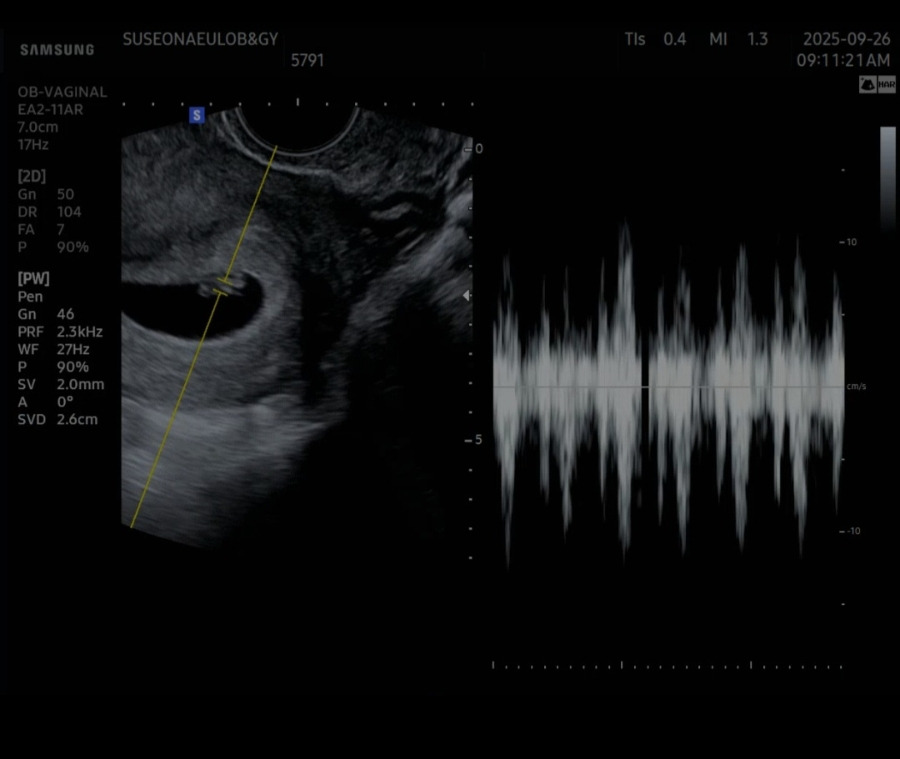

산부인과에서 초음파를 보니, 태아는 이전보다 더욱 우렁찬 심장소리를 들려주며 기특하게도 잘 뛰고 있었다. 전날 밤에 38도까지 고열이 나서 걱정했는데 다행이라고 의사에게 말씀드리자, 의사 말로는